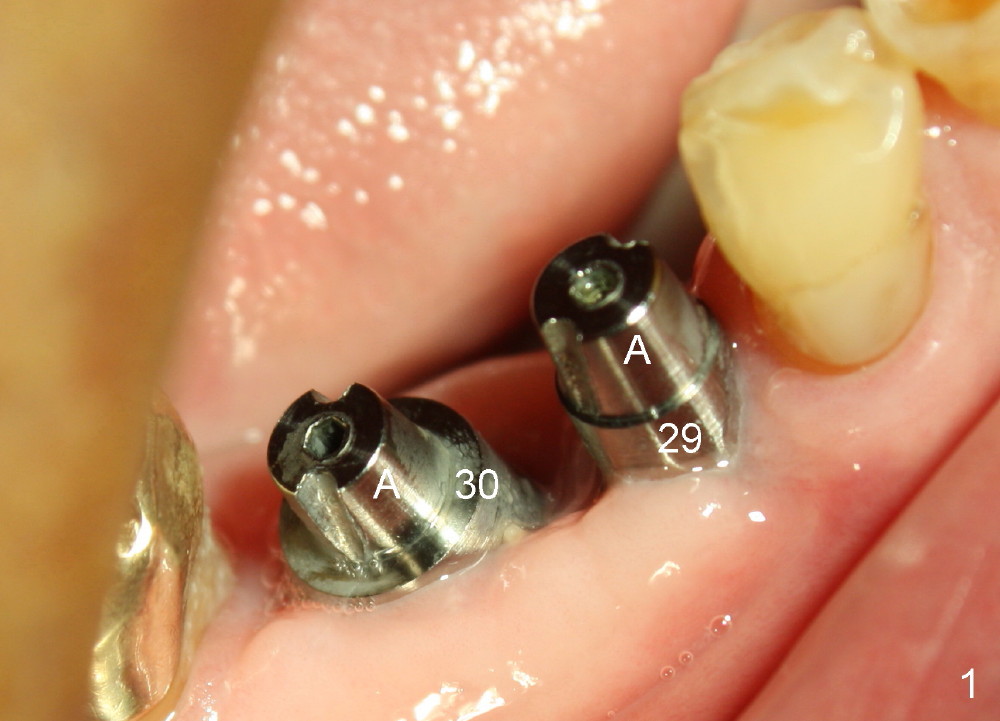

One month after implant placement at the sites of #29,30, the former is found loose (Fig.1,2). It is placed higher than #30. Three weeks later, PA is retaken to confirm that there is space apical to the implant at #29 (Fig.3 double arrows) and that there is distance from the mental loop (yellow dashed line). After infiltration anesthesia, the implant is torqued down initially (compare Fig.4,5) and more (Fig.6,7). To prevent re-loosening, the two implants are splinted (Fig.8).